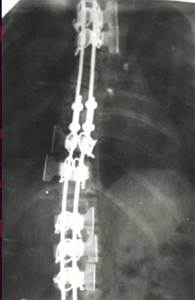

Динамический корректор. Результат на 2-е сутки после операции

В дальнейшем А.А. Гайдуков разработал и создал эндокорректор с деротационными скобами с фиксацией в блоках креплений на нескольких уровнях. Данный эндокорректор позволил эффективно на 60-100% корригировать деформацию при сколиозе III-IV степени. Но тяжелая многочасовая операция, травматичность вмешательства, проволочная фиксация и нередкие неврологические осложнения ограничивали применение данной методики.

Результат коррекции сколиотической деформации эндокорректором с деротационными скобами

Двухпластинчатый эндокорректор с многоуровневой фиксацией

Нами проведен анализ 209 случаев оперативного лечения сколиотической деформации II - IV степени с использованием двухпластинчатого эндокорректора с многоуровневой фиксацией. Срок наблюдения составил от 1 до 4-5 лет с наличием корректора и от 1 до 3 лет после его удаления. Средний возраст 13,8 года. Врожденный сколиоз был только в 3,83% случаев. Деформация с наименьшим углом по Коббу составила 21°, с наибольшим 124°. Основное число прооперированных больных было с углом искривления в диапазоне 31°-70°. Среди них у 43% угол искривления составил 51°- 60°.

У больных со II степенью деформации коррекция составила 96,56 - 100%

Больной З-ч. 13 лет Сколиотическая деформация II степени грудного отдела позвоночника. Рентгенограмма позвоночника до операции   Результат оперативного лечения. Коррекция 100%

При сколиозе III степени - 88,19 - 91,26%.

Больной П-ко, 15 лет Поясничный сколиоз III степени  Результат оперативного лечения

При сколиозе IV степени с углом деформации в диапазоне от 51° до 70° коррекция составила от 79,2 до 84,8%. С углом от 71° дог 80° - 73,3 - 86,5%. С искривлением от 81° до 122° удалось достигнуть одномоментно коррекции в пределах 72,7 - 73,8%.

Больная Л-ч, 12 лет сколиоз IV степени  Результат оперативного лечения